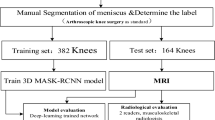

We retrospectively collected 599 knee MR images from patients with meniscal tears, and 449 knee MR images from patients without meniscal tears. All MR images were obtained from a single university hospital from January 2010 to December 2020 (mean age = 38.7 ± 16.5; M:F = 729:319). To develop the DL model for evaluating the presence of meniscal tears, all collected knee MR images of the 599 cases with meniscal tears (medial meniscus tear = 384, lateral meniscus tear = 167, medial and lateral meniscus tears = 48) and 449 cases without meniscal tears were used. Tear of the meniscus on MR images was independently assessed by two board-certified orthopedic knee specialists and repeated 2 weeks later. If there was a disagreement between the two experts, a third orthopedic knee specialist made the final decision on the grade. Reliabilities for all radiographic parameters were analyzed using intra-class correlation coefficients and were classified as little (correlation coefficient, ≤ 0.25), low (0.26–0.49), moderate (0.50–0.69), high (0.70–0.89), or very high (≥ 0.90) [22]. To develop a DL model for evaluating the type of meniscal tear, 538 cases with meniscal tears (horizontal tear = 268, complex tear = 147, radial tear = 48, longitudinal tear, 75) (Fig. 1) and 449 cases without meniscal tears were used. The study protocol was approved by the institutional research board of the university hospital. The Institutional Review Board waived the requirement for written informed consent because this study was performed retrospectively using anonymous data. The Helsinki Declaration was adhered to in this study.

This study consisted of two main components: 1) determining meniscal tears and 2) classifying tear type. In this study, we trained the model for tear detection and tear type independently.

The details of the dataset configurations are presented in Tables 3 and 4. For each case, 70% of the dataset was randomly selected as the training set, whereas the remaining 30% was assigned to the test set to evaluate the model performance.